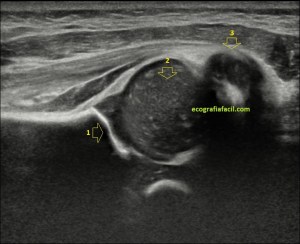

En este breve post te voy a presentar unas imágenes muy bonitas de una vesícula, en una paciente que acude a la cita de ecografía por sospecha de patología a ese nivel, con molestias anodinas e inespecíficas en el contexto de un estudio de su especialista de digestivo.

Observa las imágenes y luego te explico los hallazgos:

Cuando hice el corte longitudinal de la vesícula pude ver hasta tres patologías distintas, una adeomiomatosis (sin artefacto en cola de cometa), una litiasis vesicular y barro biliar, 2,3 y 4 respectivamente.

El caso no tiene mucho que explicar a no ser por la rareza de que se presente triple la semiología patológica en una misma imagen.

La adenomiomatosis, como un aumento de la ecogenicidad y el tamaño de la pared vesicular, la litiasis como una estructura hiperecogénica con sombra acústica posterior y el barro biliar, hiperecogénico rellenando toda la estructura ovoidea de la vesícula.

El cuello vesicular estaría afectado por la adenomiomatosis, el cuerpo por la litiasis y el barro ocuparía el fundas vesicular.

Para el estudio de la adenomiomatosis es obligado que el foco esté situado en la línea de interés, eso hará que las imágenes sean más nítidas y podamos estudiar dicha ecoarquitectura y su patología convenientemente.

Debemos observar si existiese líquido perivesicular, o signos de colecistitis. En este caso, la paciente, con estas tres patologías ya iba bien servida.

La anatomía locorregional es siempre importante, te dejo en la imagen 3 una muestra de aquella que es más importante para que intentes, en caso de que estés empezando, a reproducir dicha imagen. Ojo que la vesícula no suele estar colocada siempre tan bonita para que la veamos y hay que trabajársela, como truco, prueba a poner al paciente en decúbito lateral izquierdo.